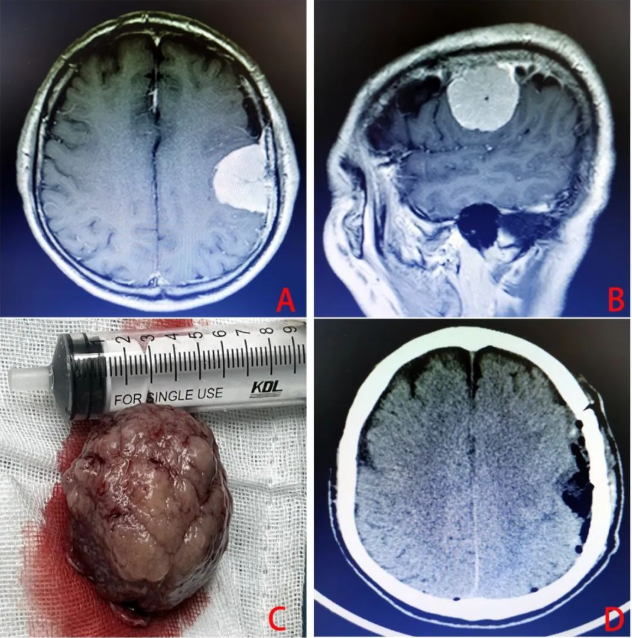

该肿瘤约鸡蛋大小,刚好生长在左侧大脑中央区(优势半球的运动及感觉中枢)上,肿瘤占位效应明显,脑组织受压移位。

在马俊的带领下,历经3小时,手术取得圆满成功。

术后患者病情平稳,未出现肢体运动及感觉障碍,恢复良好,在病区继续治疗。

脑膜瘤是神经外科常见的肿瘤之一,约占颅内肿瘤的15.31%,仅次于胶质瘤。中老年人较多,女性稍多于男性。脑膜瘤原发于蛛网膜内皮细胞,凡属颅内富于蛛网膜颗粒与蛛网膜绒毛之处皆是脑膜瘤的好发部位,矢状窦旁,大脑凸面,大脑镰旁者多见,其次为蝶骨嵴、鞍结节、溴沟、小脑桥脑角与小脑幕等部位,大部分患者是在体检过程中发现。

对脑膜瘤的治疗,以手术切除为主。原则上应争取完全切除,并切除受肿瘤侵犯的脑膜与骨质,以期根治。脑膜瘤属脑实质外生长的肿瘤,大多属良性,如能早期诊断,在肿瘤尚未侵犯周围的脑组织与重要颅神经、血管受到损害之前手术,应能达到全切除的目的。但是有一部分晚期肿瘤,尤其是深部脑膜瘤,肿瘤巨大,与神经、血管、脑干及丘脑下部粘连大紧,这些神经血管不易分离,这种情况下,不可勉强全切,以免加重脑和颅神经损伤以及引起术中大出血的危险,甚至招致病入死亡或严重残疾。对无法手术切除的晚期肿瘤,行瘤组织活检后,仅作减压性手术,以延长生命,恶性者可辅以放疗。(图文/神经外科 马元施)